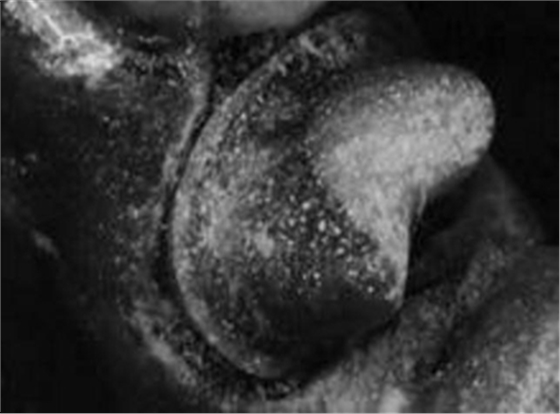

1.jpg

使用傳統(tǒng)的硅橡膠制取的印模(雙牙弓托盤)